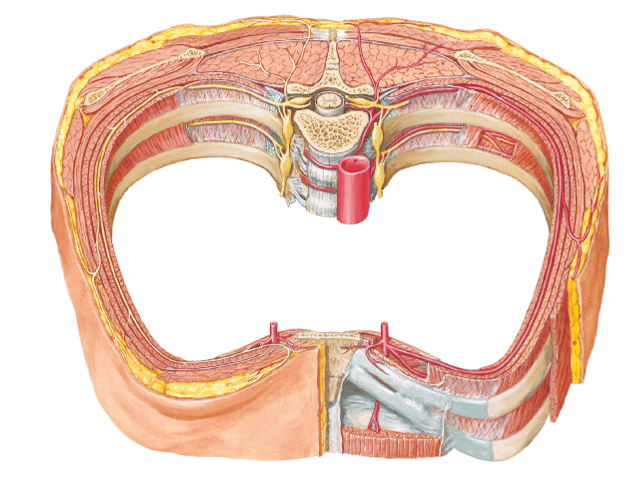

looking inside the diaphragm what can you see in the middle? what color is it? what does it serve as?

name the 3 openings of inside the diaphragm? point them out in picture

which hole opens through the central tendon?

central tendon

white

muscles all converge here on this central circle

central tendon is the upside down C

caval foramen is the big hole...opens up through the central tendon

esophageal hiatus is the oval oblong hole in center and inferior

aortic hiatus is the hole where you can even see part of the aorta coming through...most posterior of the 3 openings

what passes through these openings in the diaphragm?

Openings:

- Caval foramen...Inferior vena cava

- Esophageal hiatus...esophagus

- Aortic hiatus...Aorta

the sternal region of the diaphragm has attachments where?

the costal part has attachments where?

the lumbar part has attachments where?

Regions:

- Sternal part...attachments “along sternum”

- Costal part...attachments “along ribs”

- Lumbar part...attachments “along quadratus lumborum and psoas”

in picture: all regions form around the central tendon...small spot above is the sternal part...two huge kidney shapes on sides of central tendon are the costal regions...and the lumbar region is the space underneath the central tendon